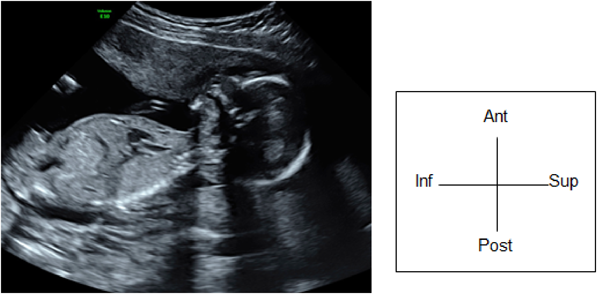

(4) Ventricular Tachycardia

When ventricular tachycardia does not involve retrograde conduction (ventriculo-atrial conduction), atrial and ventricular contractions dissociate. Dissociation between atrial and ventricular contractions also occurs in patients with junctional ectopic tachycardia.

When the atria and ventricles contract at a 1 : 1 ratio due to retrograde conduction (ventriculo-atrial conduction), ventricular tachycardia needs to be distinguished from supraventricular tachycardia. Ventricular tachycardia is a rare form of arrhythmia in the fetal period. No established treatment is available in hand. Its pathological condition should be carefully determined in each patient prior to attempting treatment. Short-term magnesium administration is one approach to take. Intravenous lidocaine and the maternal administration of oral propranolol or mexiletine are other options. When long QT syndrome or torsade de pointes is suspected, flecainide, sotalol, and amiodarone should not be administered as they can exacerbate the QT prolongation.3)